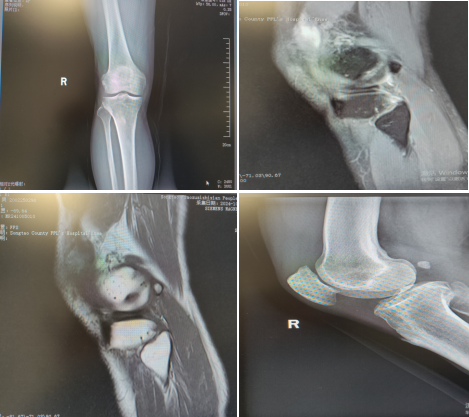

一次不慎摔倒,导致右膝肿痛、无法活动——十天来,这成了71岁龙奶奶的烦心事。在家自行用药未见好转后,她来到县人民医院关节外科求助。

术前检查

经诊断,龙奶奶为“右髌骨骨折”,随即被收治入院。科室团队迅速完成术前评估与准备,并为其实施“右侧髌骨骨折切开复位内固定术”。手术顺利,术后龙奶奶恢复良好,膝部肿胀与疼痛日渐减轻。

术后复查DR